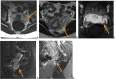

Nutcracker phenomenon is the descriptor for a patient's anatomy whenever the left renal vein becomes compressed between the abdominal aorta and the superior mesenteric artery. Nutcracker syndrome is the terminology used when the nutcracker phenomenon is accompanied by symptoms including pain (abdominal, flank, pelvic), hematuria, and orthostatic proteinuria. Diagnosis can be made with Doppler ultrasound, venography, computed tomography, or magnetic resonance imaging. This case demonstrates some of the typical findings of nutcracker syndrome. The limited clinical features and interesting imaging findings, in addition to the young age of the patient, make this a notable case.